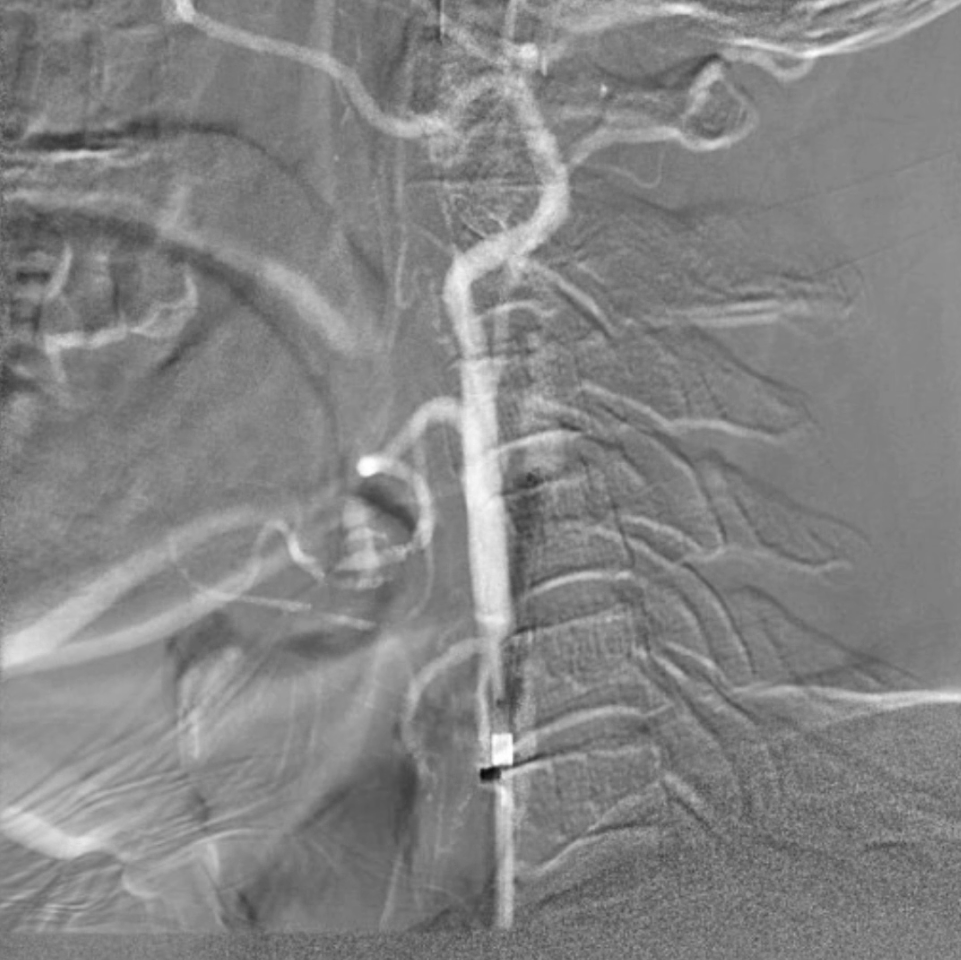

预扩张与支架植入:匹配病变特点的器械选择

预扩张:使用5/30mmAviator球囊,扩张前需将患者心率提升至80次/分以上(避免扩张时迷走神经反射导致心率骤降);

支架选择:选用8/40mmPRECISE开环支架,其柔顺性好,适合迂曲的颈动脉解剖结构,定位精准且完全覆盖病变。

血供改善与安全性验证

造影显示:支架膨胀良好,无需后扩张;

颅内血供:左侧颈内动脉血流通畅,因右侧闭塞,左侧成为全脑主要供血通路,血供恢复满意